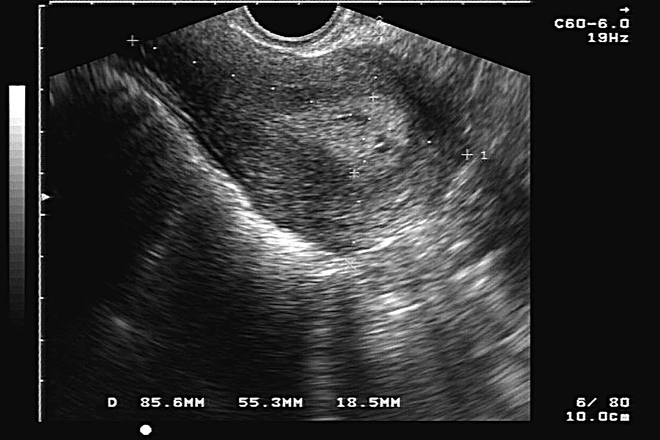

Abordaje diagnóstico por imagen en patología benigna de la vesícula y vías biliares

El ultrasonido es el método de imagen inicial recomendado para la evaluación de pacientes que se presentan con síndrome ictérico o con dolor en el cuadrante superior derecho debido a la capacidad del ultrasonido para evaluar órganos adyacentes y a su capacidad de localizar sitios